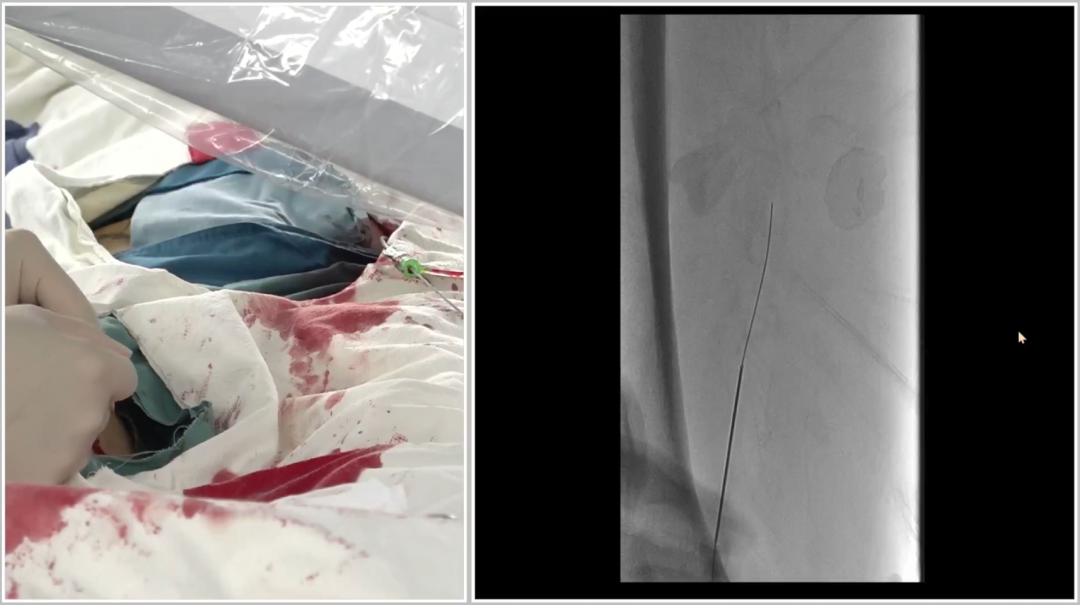

管腔准备与支架植入

预扩张:使用球囊扩张病变段,造影提示长段限流性夹层,需支架覆盖

治疗模式:因股腘动脉直径<4.5mm,选择DCB(药物涂层球囊)+BMS(裸金属支架)联合方案;

支架选择:在DCB扩张导管进行管腔准备后,植入2枚5mm INNOVA支架,其优势在于尾端定位精准,尤其适合累及开口或分叉的病变。

6

手术结果:

血流通畅,解剖与功能双重改善

最终造影显示:支架定位准确、形态良好,股浅动脉、腘动脉及膝下动脉显影清晰,血流通畅。